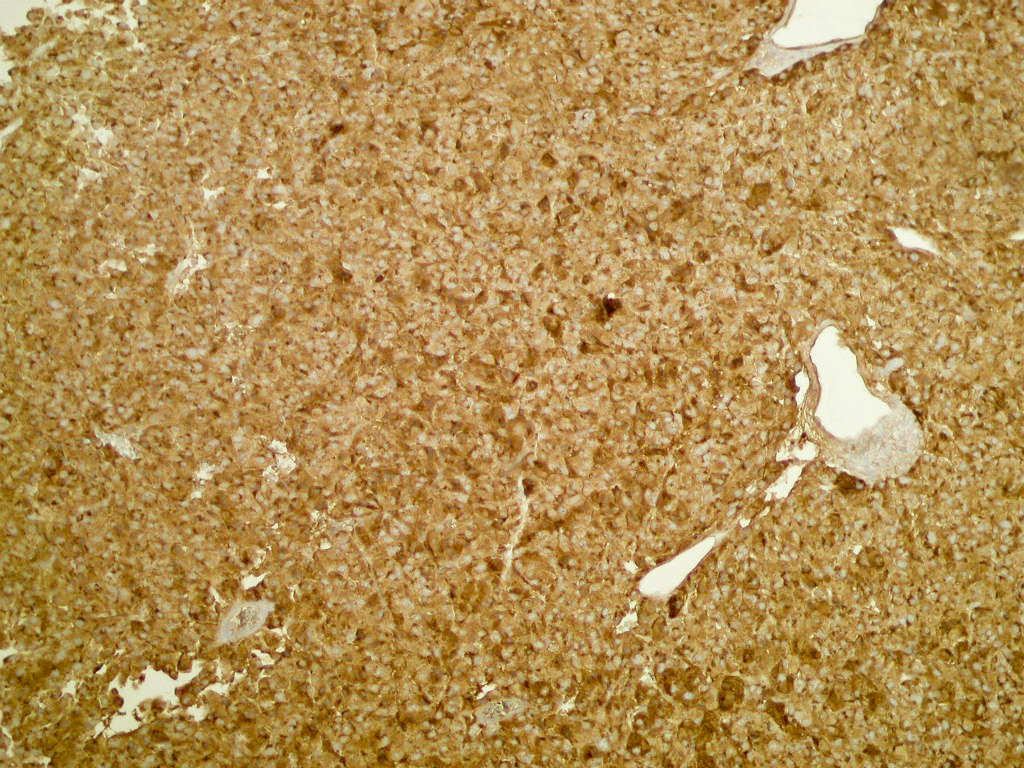

Microscopic (histologic) description

- Typical morphology: epithelioid cells with abundant, eosinophilic / amphophilic, granular cytoplasm and round / ovoid, vesicular / salt and pepper nuclei, arranged in a nested / zellballen pattern and separated by fibrovascular septae with sustentacular cells (Am J Surg Pathol 2004;28:94, World J Clin Cases 2014;2:591, Endocr Pathol 2022;33:90)

- May have focal pleomorphism, nuclear hyperchromasia, low mitotic activity or clear cytoplasm

Microscopic (histologic) images

Contributed by Theodorus H. van der Kwast, M.D., Ph.D., Michelle R. Downes, M.D., Debra L. Zynger, M.D. and David Cohen, M.B.B.Ch., M.D.

Positive stains

- INSM1 (diffuse), chromogranin A (variable, often diffuse), synaptophysin (variable, usually diffuse) (Endocr Pathol 2022;33:90)

- GATA3

- SSTR2 (Hum Pathol 2019:86:66)

- TH, DBH in functional paragangliomas

- SDHB loss (absence of granular cytoplasmic labeling) if SDHB mutation

- SDHA loss (absence of strong diffuse granular cytoplasmic labeling) if SDHA mutation

- Sustentacular cells: S100, SOX10